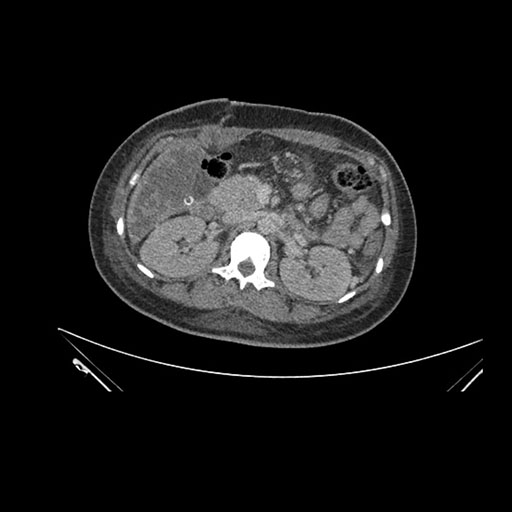

Axial Arterial

Axial Venous

Imaging analysis

Based on initial findings, which issue(s) would you be most concerned about?